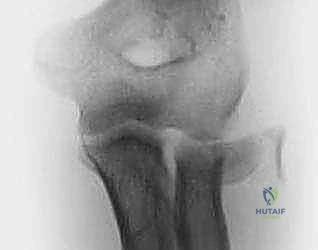

- الأشعة السينية (X-rays): يتم أخذ صور بأوضاع مختلفة (أمامي خلفي، جانبي، ومائل) لرؤية الكسر بوضوح. أحياناً يكون الكسر دقيقاً جداً ولا يظهر إلا من خلال علامة "وسادة الدهون المرفوعة" (Positive Fat Pad Sign) التي تشير إلى وجود نزيف داخل المفصل.

- الأشعة المقطعية (CT Scan): في حالات الكسور المفتتة أو المعقدة، يطلب الدكتور هطيف إجراء أشعة مقطعية ثلاثية الأبعاد (3D CT) لبناء تصور هندسي دقيق للكسر، مما يساعده في تخطيط العملية الجراحية واختيار الشرائح والمسامير المناسبة قبل دخول غرفة العمليات.